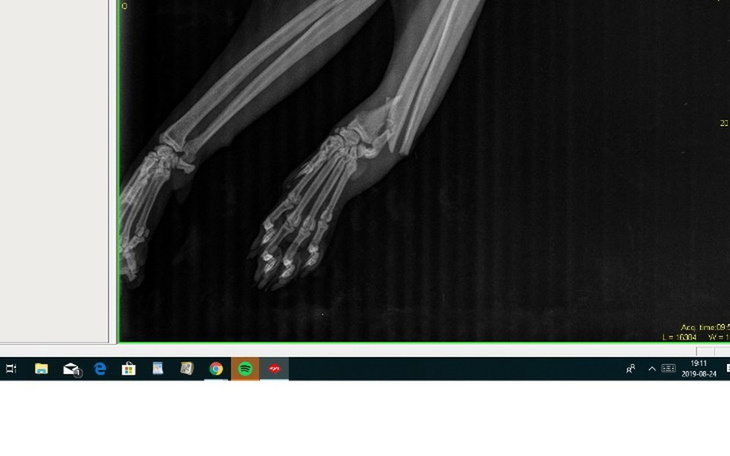

Moi drodzy, jesteśmy już po operacji. Lekarz mówił, że była dość skomplikowana i nie do końca udało się pozbierać łapę w jedną całość...mimo wszystko i tak się cieszę z efektu. Została zastosowana specjalna płytka tytanowa blokowana. Teraz wszystko zależy od gojenia się, tkanki były dość mocno uszkodzone, nadal jest obrzęk, podajemy lekarstwa i w poniedziałek wybieramy się na wizytę kontrolną :)